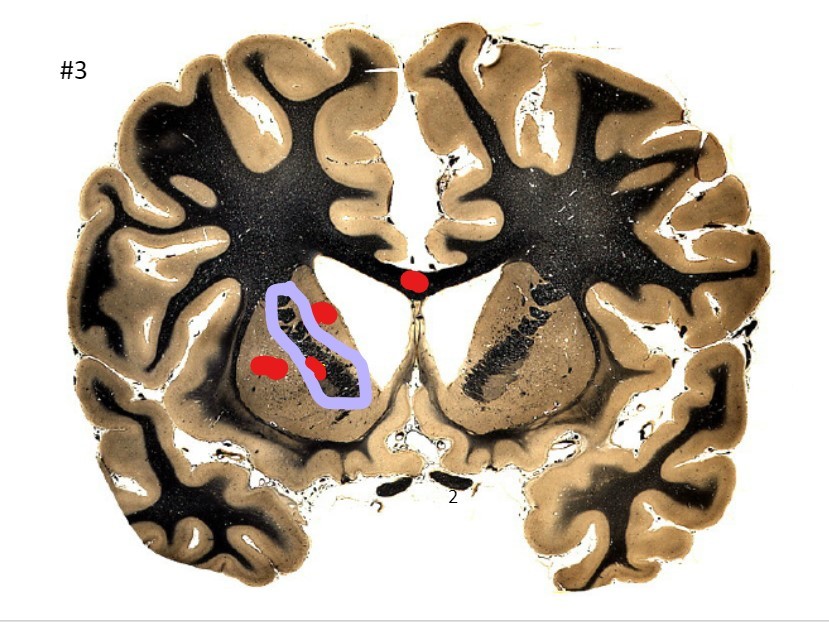

what is the circled area (#3)?

A

the corpus callosum

Q

the caudate nucleus

7

the internal capsule

8

the putamen

9

the optic nerve